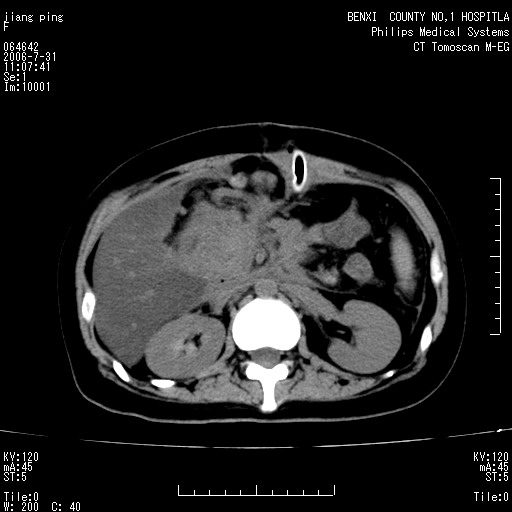

以下是引用晓杰在2006-8-1 9:01:00的发言:[br]支持营养不良导致脂肪肝。[br]胰头增大界限不清,考虑为胰腺炎破坏十二指肠粘膜、肠壁增厚、肠腔狭窄,并与胰头粘连所致

以下是引用jiajie在2006-7-31 20:34:00的发言:[br]支持营养不良导致脂肪肝。[br]胰头增大界限不清,考虑为胰腺炎破坏十二指肠粘膜、肠壁增厚、肠腔狭窄,并与胰头粘连所致。